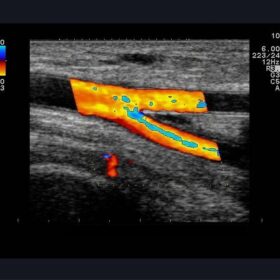

Ultrasound Aloka Prosound Alpha 10 – Image Gallery and Videos

Enhanced image quality ensures more accurate and efficient diagnosis while increasing patient satisfaction. The ideal choice for a large office or hospital imaging department. The Alpha 10 combines a 12 Bit A/D digital beam converter. High powered image processing channels and the exclusive probe technology to take examinations to the next level.

Sophisticated beam control provides high resolution and penetration while minimizing image degradation. While user-oriented operability and ergonomics create the ideal environment for fast and accurate imaging and diagnoses. The Alpha 10’s Extended Pure Harmonic Detection is a digital pure beam-imaging platform. That incorporates state-of-the-art acoustic technology that dramatically improves the clarity of the ultrasound beam formation and signal processing.